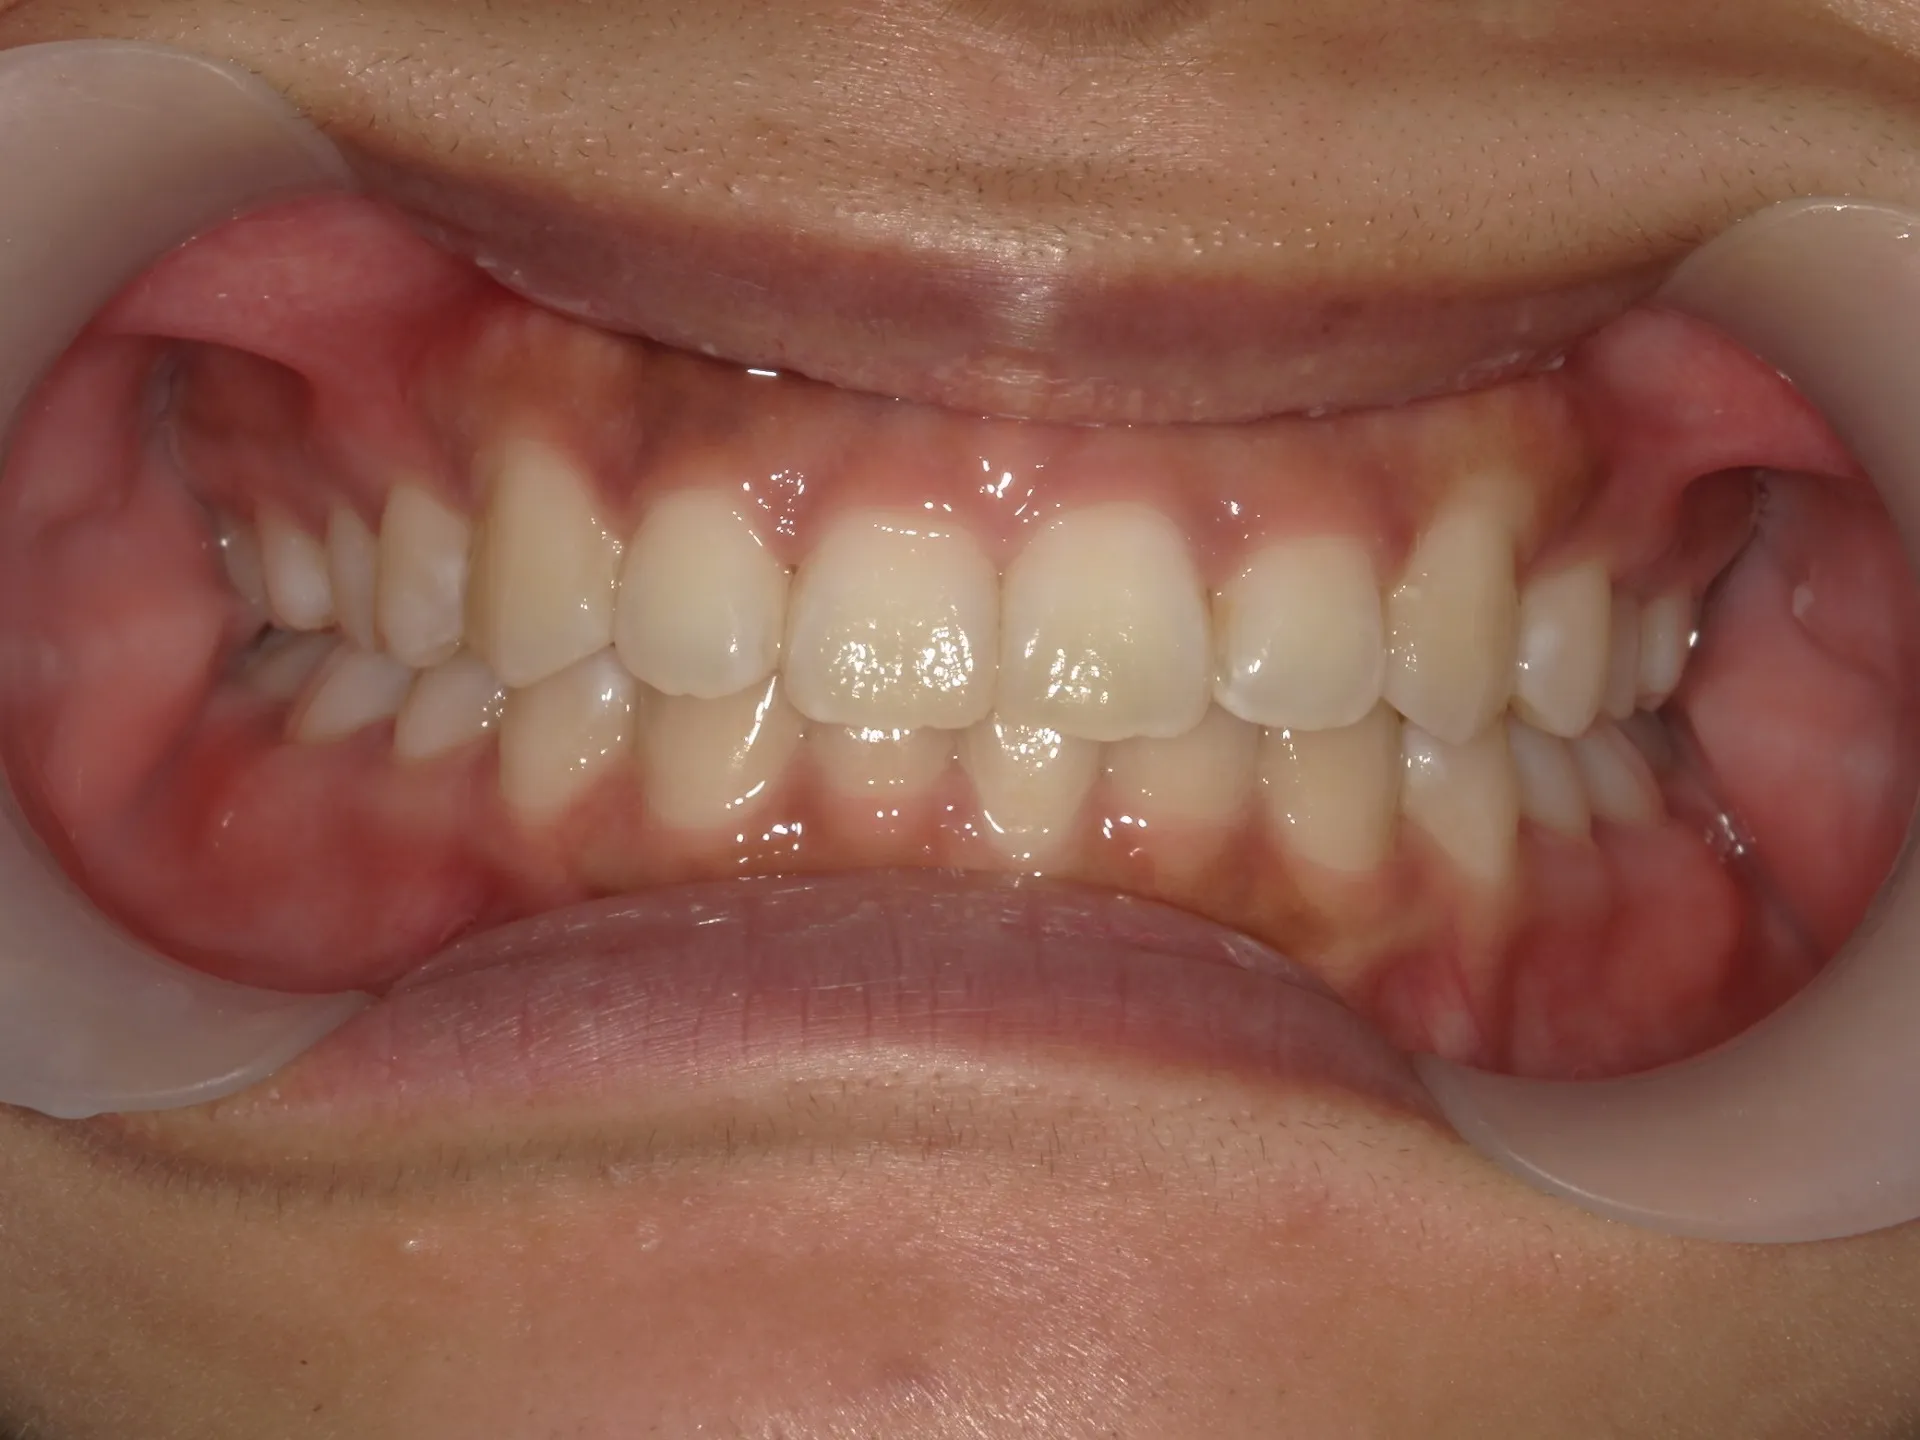

内側に倒れた前歯を矯正で正す!

前歯が内側に倒れてたりしませんか?

または2番目の歯が外側に飛び出していませんか?

この2つはよく同時に起こることがあります。

今回はインビザライン矯正治療(マウスピース矯正)で治療した症例についてご紹介いたします。